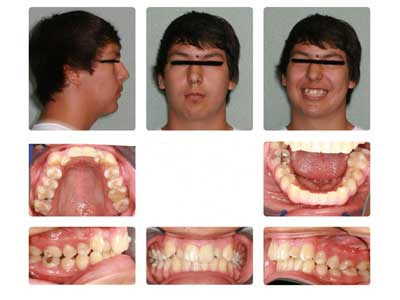

Case report A healthy 16-year-old male presents with Class II bite, an obtuse nasolabial angle, a slight, long concave profile with deficiency in the growth of the mandible, and inadequate spacing for the maxillary teeth. What are the options and talking points for this treatment plan?1. There is likely very little growth potential left in this patient, so trying to capture any remaining growth would be minimal.

2. If we were to focus only on the occlusion (minus profile, etc.), then it would be simple to extract the maxillary 4’s (1st bicuspids) and then acquire a somewhat ideal alignment of the arches.

3. In reference to point No. 2, orthodontic treatment planned without mandibular jaw advancement surgery in these types of cases generally will build in more dental compensations for skeletal variation (2), as the profile is compromised even more with a wider nasolabial angle, longer profile, and thus limiting the ability for any future facial profile correction.

4. The ideal treatment and recommendation would be to perform a lower jaw advancement surgery to give an ideal position of skeletal and dental components. Worms et al. reported that the total interrelationships of surgical and orthodontic contributions are in the best care and interest of the patient long term. (2)

6. If surgery is not an option or desired at that time, then many would consider again not to extract the upper 4’s and use a functional appliance, such as a Herbst to attempt to advance the mandible while aligning the teeth as best as possible. In the end, however, there would likely be excess overjet of the anterior teeth in this type of compromise.

It could be concluded with the aforementioned talking points that there is not a right or wrong way to proceed in cases like this. Some options are better than others, but this is the take-home point: If a Class II patient (as presented herein) does have the upper 4’s removed, it exacerbates the existing profile and limits virtually any potential for a correction of profile in the future. It is, therefore, vital to discuss all risks, benefits, complications, and alternatives so the patient can make the best decision possible. Assuming no regard to cost or possible complications, the mandibular advancement would be considered by most to be the preferential treatment in this case, as it resolves the core problem — mandibular deficiency. In this case, the patient was not willing to undergo a surgical procedure at this time, so the treating orthodontist advised the family against the removal of maxillary teeth in order to preserve facial profile and allow for possible future mandibular advancement procedure.